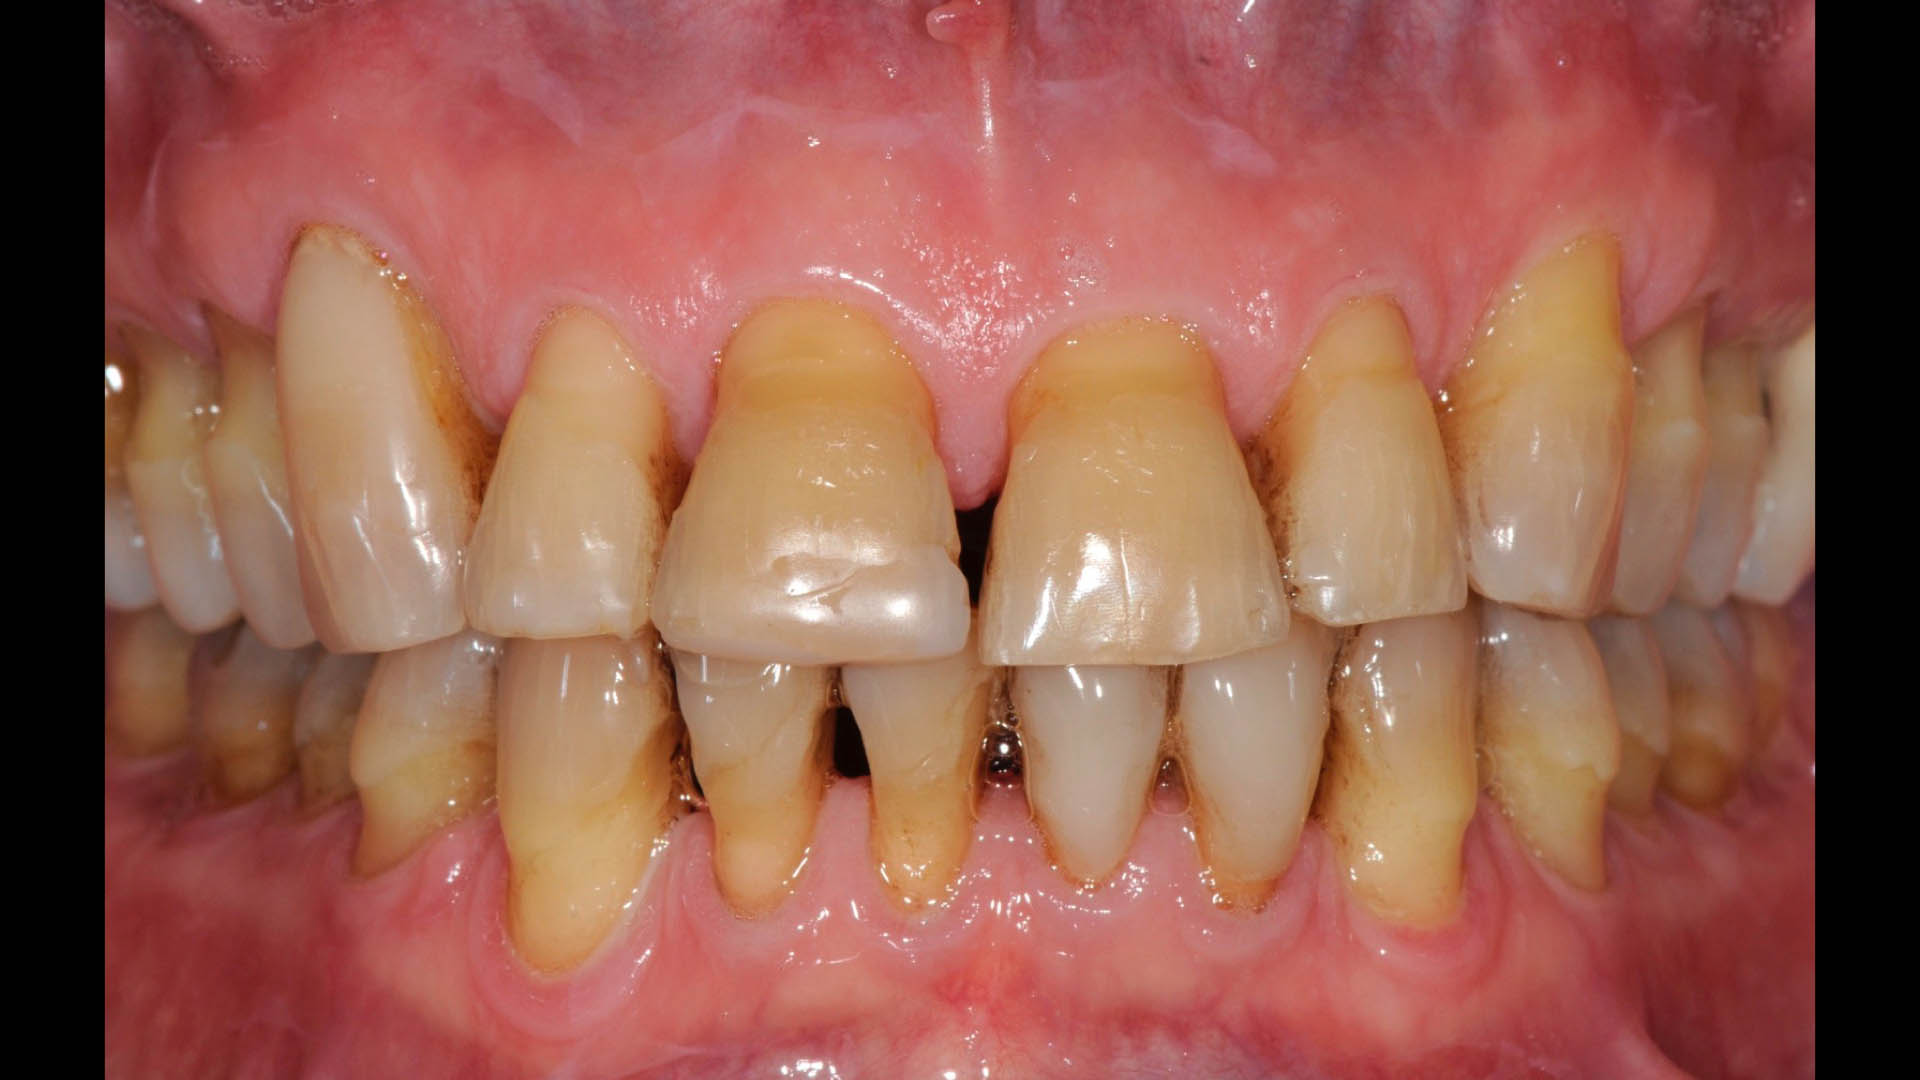

Take a glimpse into the magic of Coral Gables Dentistry through our before and after pictures. See firsthand the incredible smile makeover transformations that have brought confidence and joy to our patients.